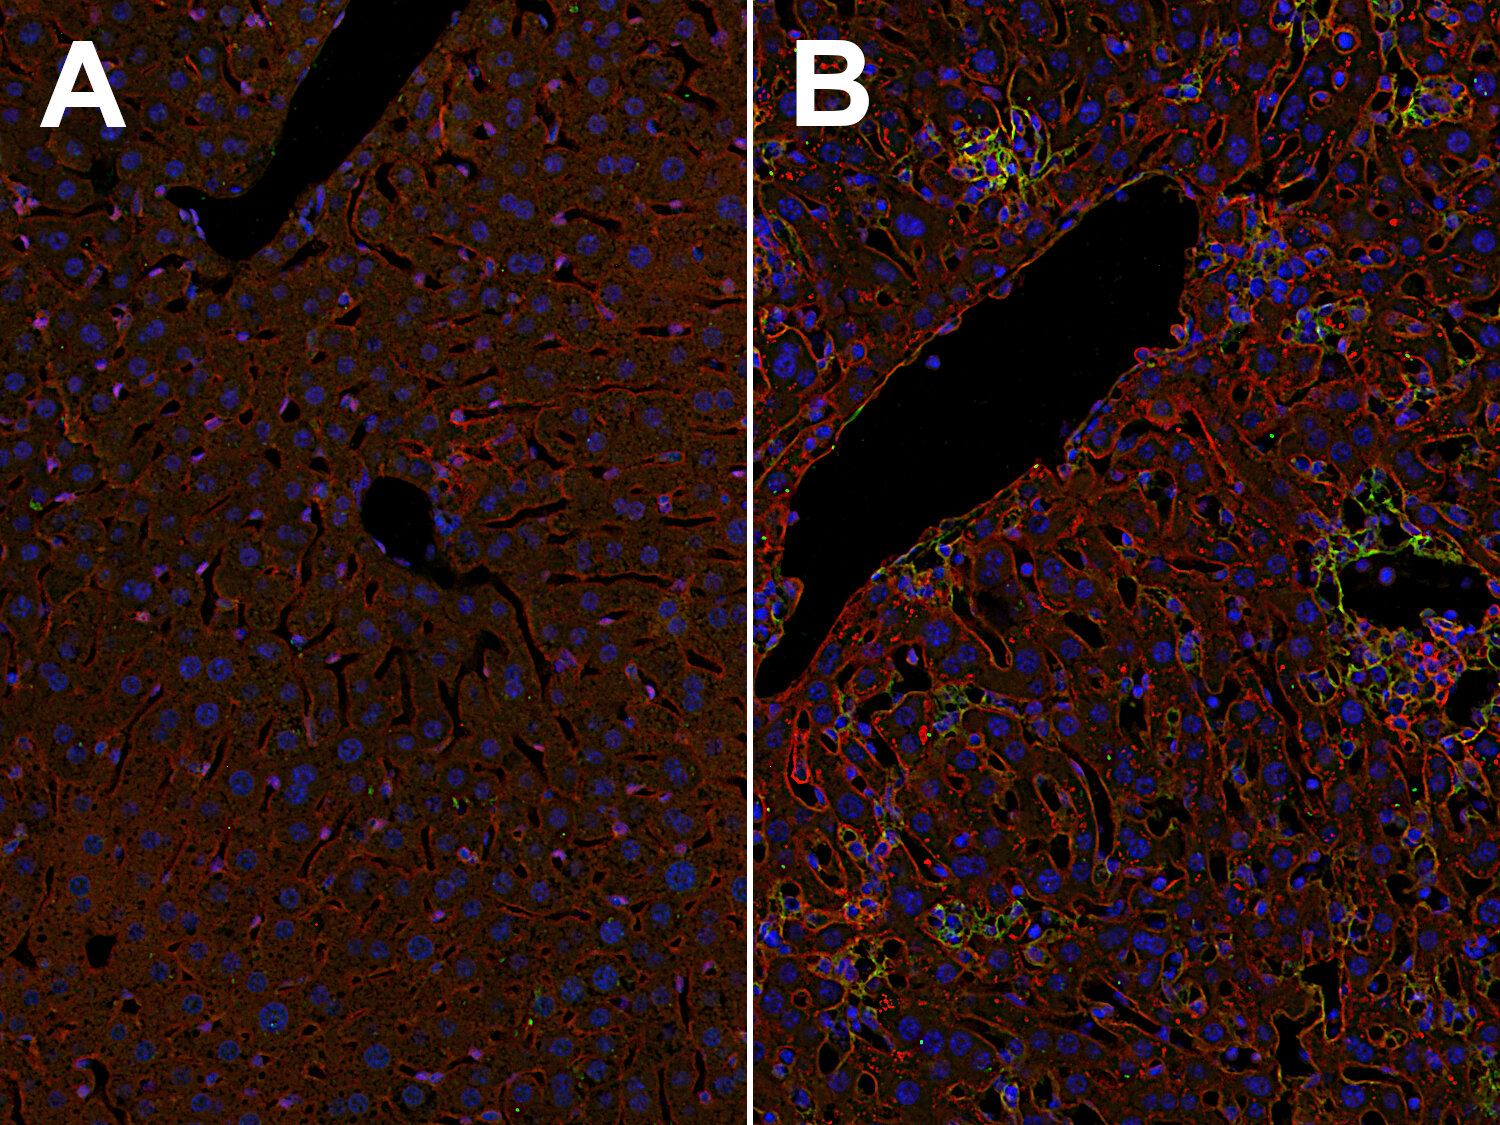

Inflammatory cytokines, including TNFα, IL-1β, and IFNγ, strongly upregulate the expression of ICAM1 and VCAM1, not just on endothelial cells, but also on other cell types, e.g., fibroblasts and inflammatory macrophages (Hosokawa et al., 2006, Wiesolek et al., 2020). Elevated ICAM1 and VCAM1 expression levels are found, for example, on liver sinusoidal endothelial cells and in multifocal mononuclear cell aggregations in the liver of a mouse infected with Toxoplasma (T.) gondii (Figure 2).

Indirect immunostaining of formalin fixed paraffin embedded (FFPE) mouse liver sections of a non-infected mouse (A) and a T. gondii-infected mouse (B) with rabbit anti-ICAM1 antibody (cat. no. HS-532 003, dilution 1:500, red) and guinea pig anti-VCAM1 antibody (cat. no. HS-470 004, dilution 1:500, green). Nuclei have been visualized by DAPI staining (blue).

Figure 2: Elevated ICAM1 and VCAM1 levels on liver sinusoid endothelial cells and in multifocal mononuclear cell aggregations in the liver of a mouse infected with T. gondii. Indirect immunostaining of formalin fixed paraffin embedded (FFPE) mouse liver sections of a non-infected mouse (A) and a T. gondii-infected mouse (B) with rabbit anti-ICAM1 antibody (cat. no. HS-532 003, dilution 1:500, red) and guinea pig anti-VCAM1 antibody (cat. no. HS-470 004, dilution 1:500, green). Nuclei have been visualized by DAPI staining (blue).